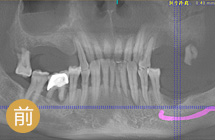

手术成功原理:针对缺牙引起牙槽骨萎缩吸收的情况,通过GPR植骨和保持位点手术形成新的牙槽骨。再通过数字化种牙完成前牙美学区的植入,实现即刻负重,拥有良好的美学效果… [详细]

前牙美学度高

植体结合稳固

术后就能吃饭

远期成功率高